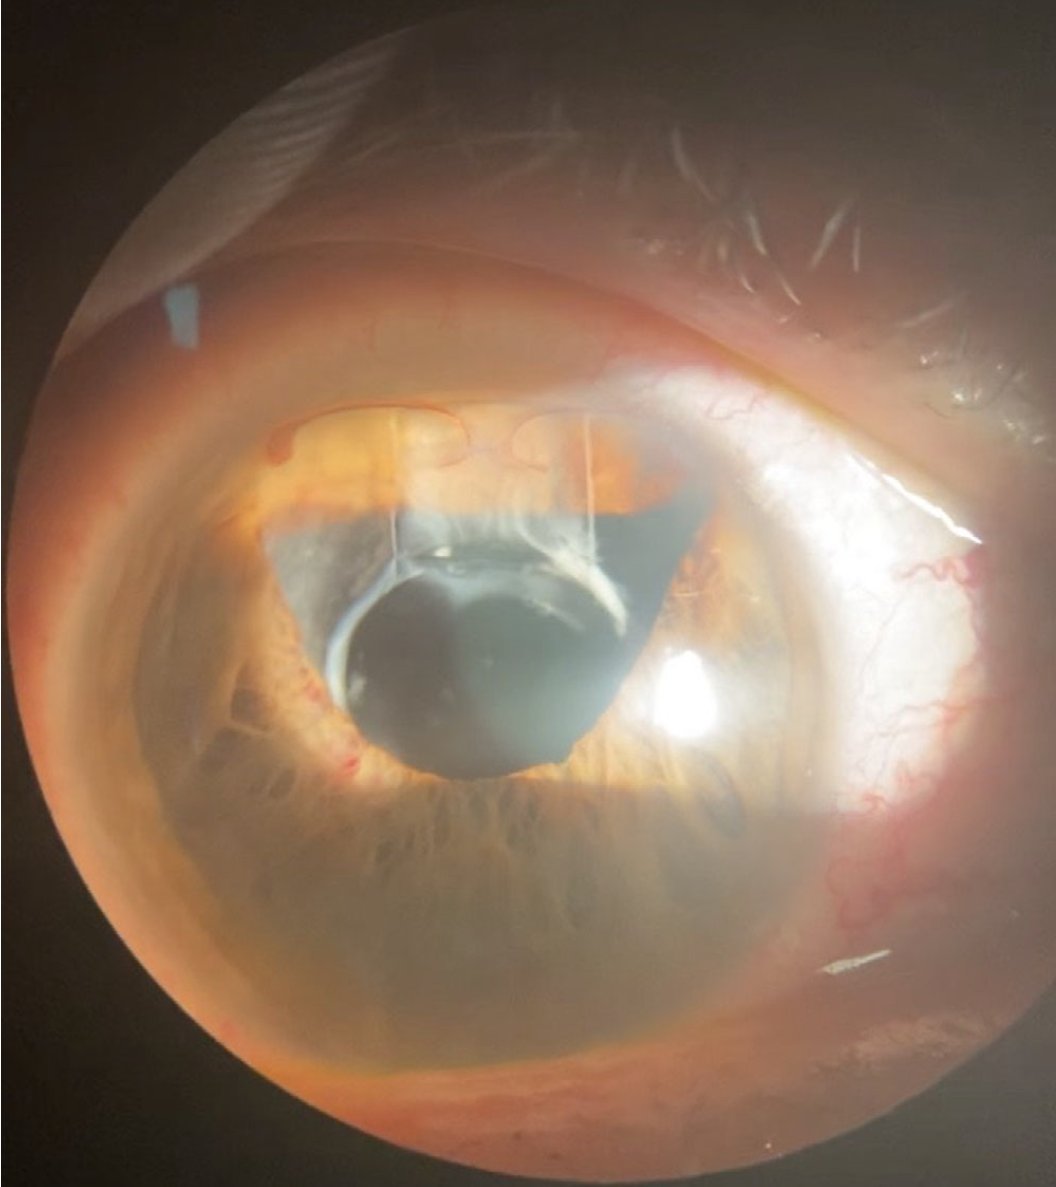

眼内レンズ脱臼

・細隙灯検査により、眼内レンズ脱臼が明らかになった

◦前房出血/網膜剥離の所見は認めなかった